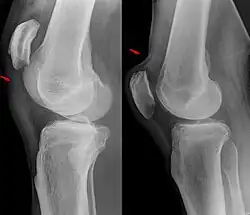

Weitere Bildbeispiele

-

Kompletter Riss mit tief stehender Patella -